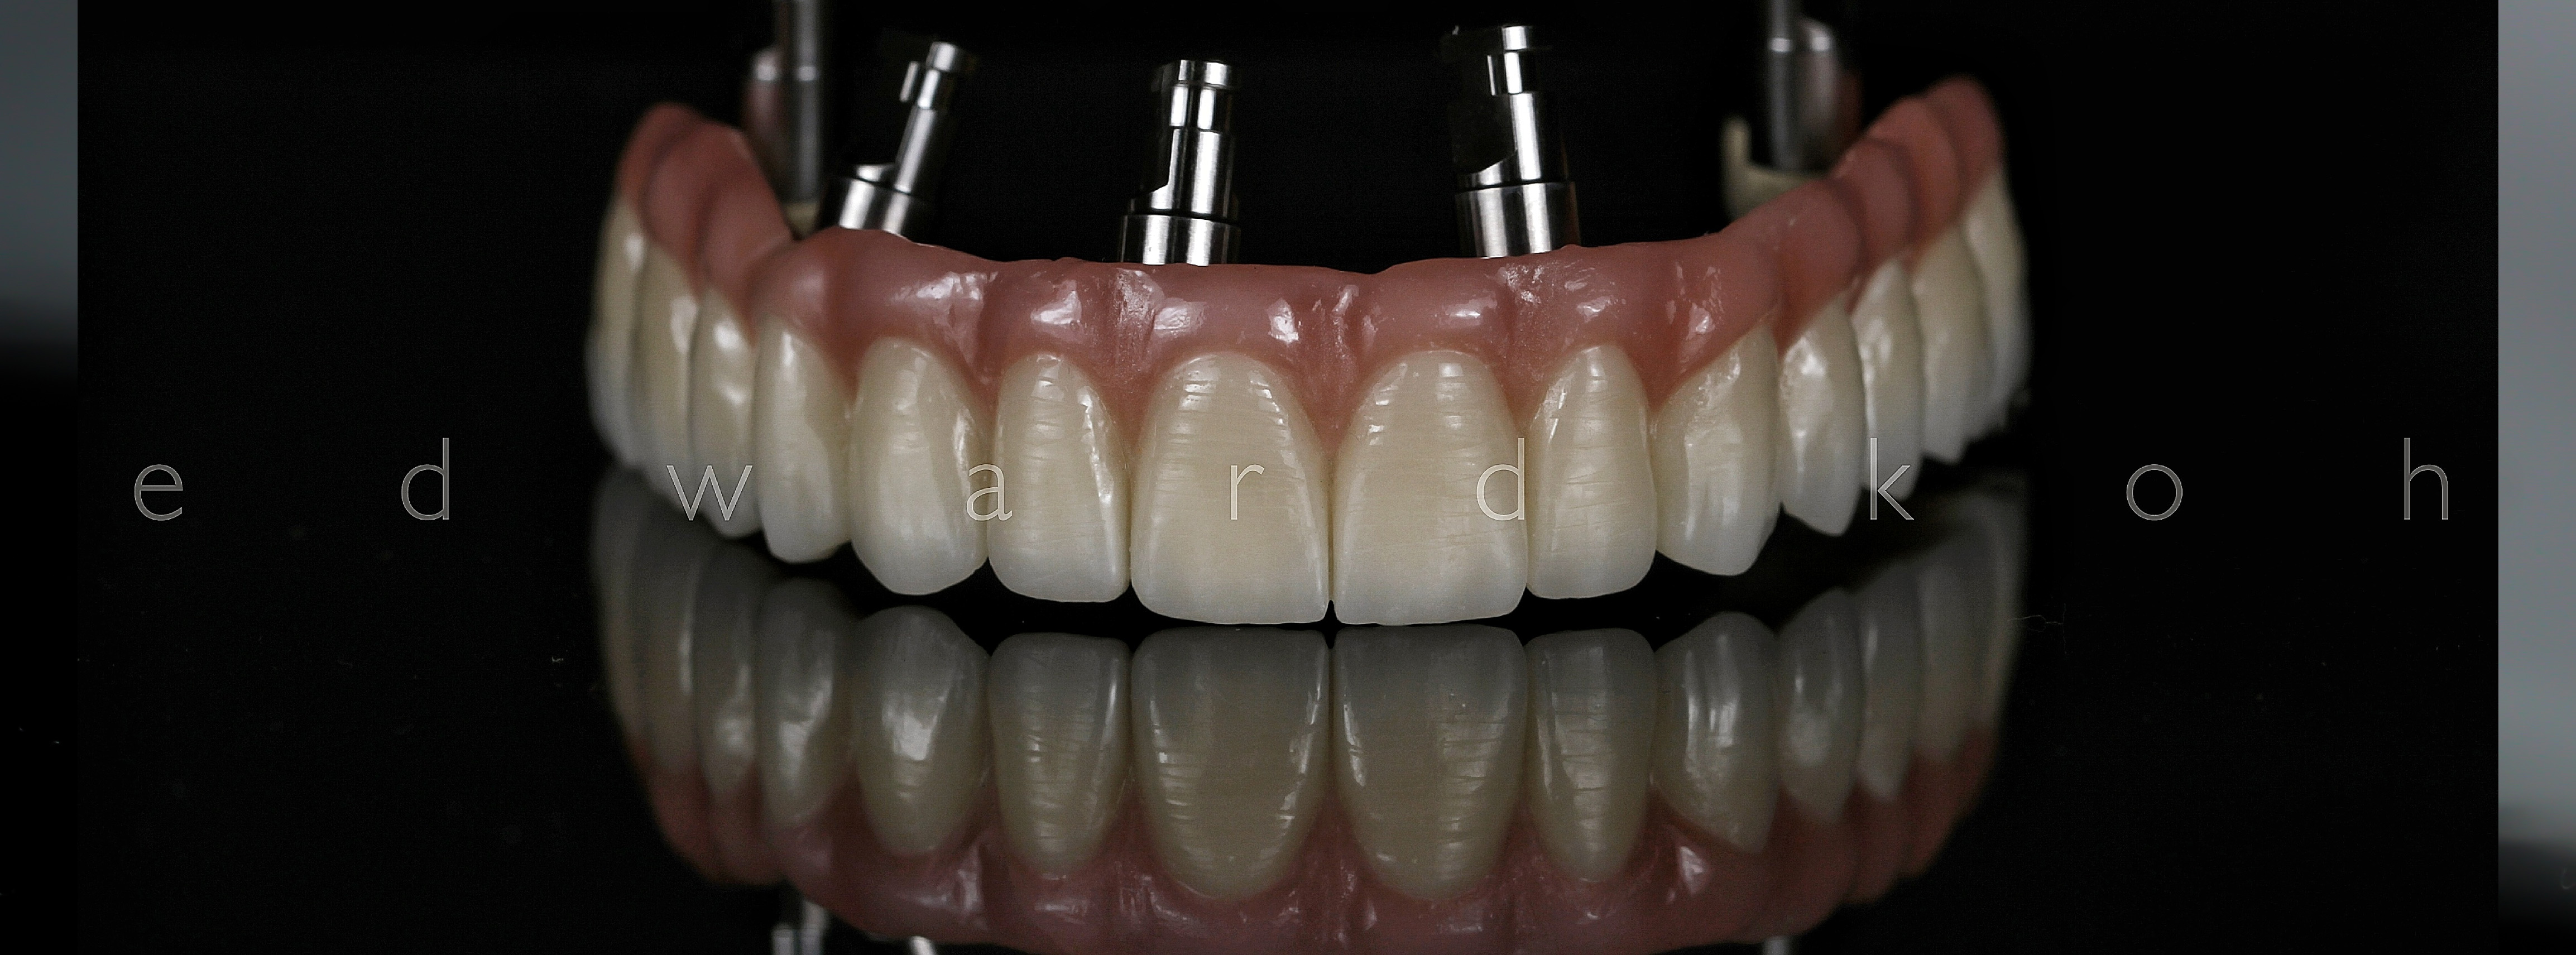

A perda de dentes pode levar a problemas estéticos, de oclusão (mordida) e perda óssea. Portanto é fundamental uma rápida reposição do elemento perdido. Os Implantes Dentários são parafusos de titânio que substituem a raiz dos dentes perdidos. O implante dental serve de apoio para a prótese (coroa) que deve ser semelhante aos dentes: naturais em estética e função. Os Implantes Dentários podem ser indicados para repor a perda de todos os dentes, de alguns ou de apenas um dente.

Em alguns casos, os implantes podem ser utilizados para suportar a prótese logo após sua instalação, num procedimento conhecido como carga imediata, por meio do qual podemos fazer reabilitações totais ou parciais.

O Implante Dentário inibe a atrofia do osso após a perda de um dente; é fixo e não há necessidade de comprometer os dentes naturais adjacentes.